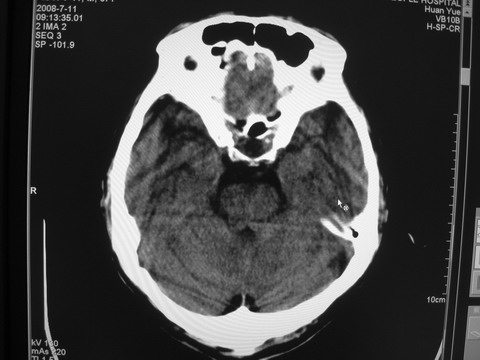

患者 男 69岁 头晕头痛不适

多发病灶,指状水肿,首先诊断转移瘤。

多个结节并周围大面积水肿区,多考虑多发性脑转移瘤

小病灶、大水肿,病灶多发,首先考虑多发转移瘤;建议查原发灶。

额顶叶多发小病灶、大水肿,首先考虑多发转移瘤;建议查原发灶

脑内多发病灶,小病灶,大水肿。

典型转移性肿瘤。

应进一步检查,查找原发病灶。

结果 : 该患者结肠癌病史5年 考虑脑转移